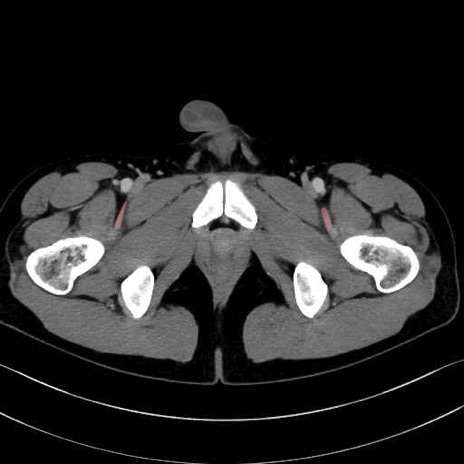

4. 深層外旋六筋(股関節の深部)

梨状筋 (Piriformis)

内閉鎖筋 (Obturator internus)

外閉鎖筋 (Obturator externus)

大腿方形筋 (Quadratus femoris)